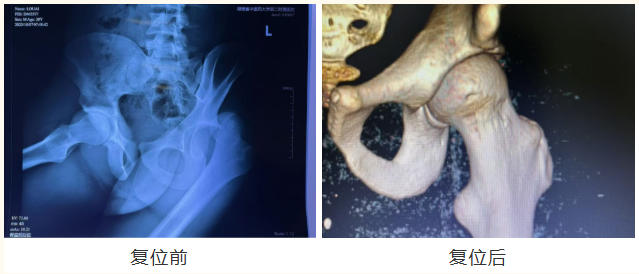

据湖南中医药大学第二附属医院湖湘张氏中医骨伤治疗中心主任、骨伤五科主任阮红良介绍,髋关节脱位的急性闭合复位黄金时间为伤后12小时内。考虑到阿米尔同时伴有左髋臼骨折与左小腿胫骨骨折,医疗团队为他制定了急诊下左髋关节脱位手法整复术及中医特色的左胫骨骨折手法整复小夹板外固定,择期行髋臼骨折切开复位内固定术。

与此同时,一位中医师细询问病史,仔细体格检查,积极联动各科室为急诊手术做好各项准备。入院3小时后,骨伤五科医疗团队立即对阿米尔施手法复位治疗,在全麻下行左髋关节切开复位内固定术,复位过程中,医务人员运用 “拔伸牵引、端提捺正” 的张氏正骨手法,稳、准、轻、巧地施加外力,顺利将脱位的髋关节复位。当 “咔哒” 一声轻响传来,阿米尔明显感到疼痛骤减,紧锁的眉头终于舒展。手术进展顺利,病人平安返回病房。